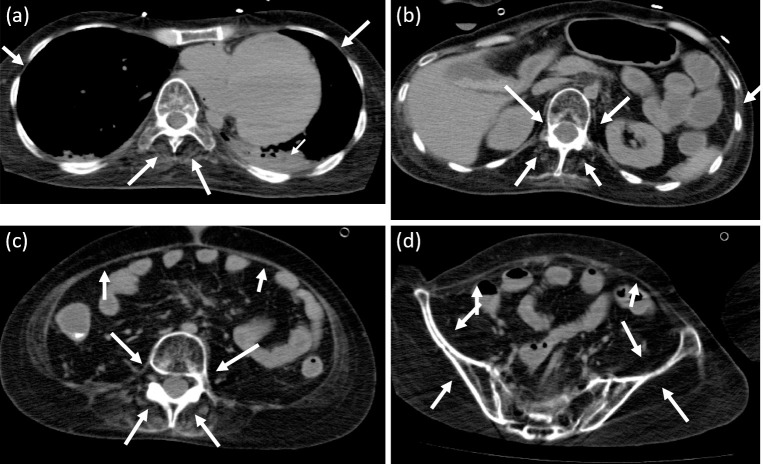

我们描述的情况下,25岁的男性杜氏肌营养不良症和急性肾损伤谁是接受机械通气。在肾功能恢复期间,使用基于肌酐、胱抑素C和菊粉水平的公式评估患者估计的肾小球滤过率(eGFR)。基于肌酐的eGFR在整个研究期间都非常高。基于胱抑素c的eGFR也高于菊粉清除率。这些发现表明,除了肌肉量减少外,在脂肪量极度减少的患者中,基于胱抑素c的eGFR也可能超过菊粉清除率。

We describe the case of a 25-year-old male with Duchenne muscular dystrophy and acute kidney injury who was receiving mechanical ventilation. The patient's estimated glomerular filtration rate (eGFR) was assessed using formulas based on creatinine, cystatin C, and inulin levels over time during the recovery of his renal function. The creatinine-based eGFR was extremely high throughout the study period. The cystatin C-based eGFR was also higher than the inulin clearance. These findings suggest that cystatin C-based eGFR may also exceed inulin clearance in patients with an extremely reduced fat mass, in addition to a reduced muscle mass.